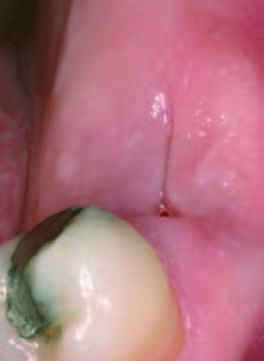

15日後歯肉の状態

抜歯後にできた穴にPRGFを注入すると、上皮や骨の再生が促進され、短期間で穴が塞がります。また、抜歯後の痛みや腫れも軽減されるため、回復がスムーズに進みます。

一方、自然治癒の場合、穴が完全に塞がるまでに数ヶ月かかることがあります。その間に、ドライソケット(抜歯窩治癒不全)を引き起こしたり、食べ物が詰まることで痛みや悪臭が発生することもあります。